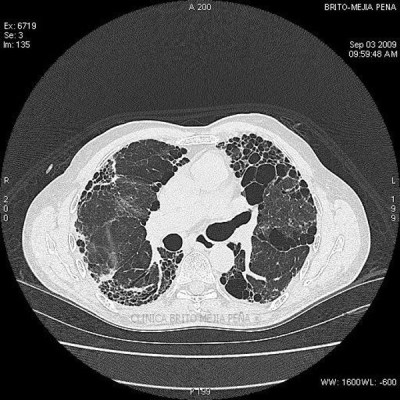

Fibrosis y enfisema pulmonar